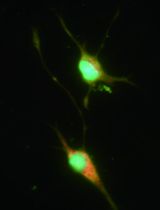

Cover of eLIFE, featuring study using the protocol.